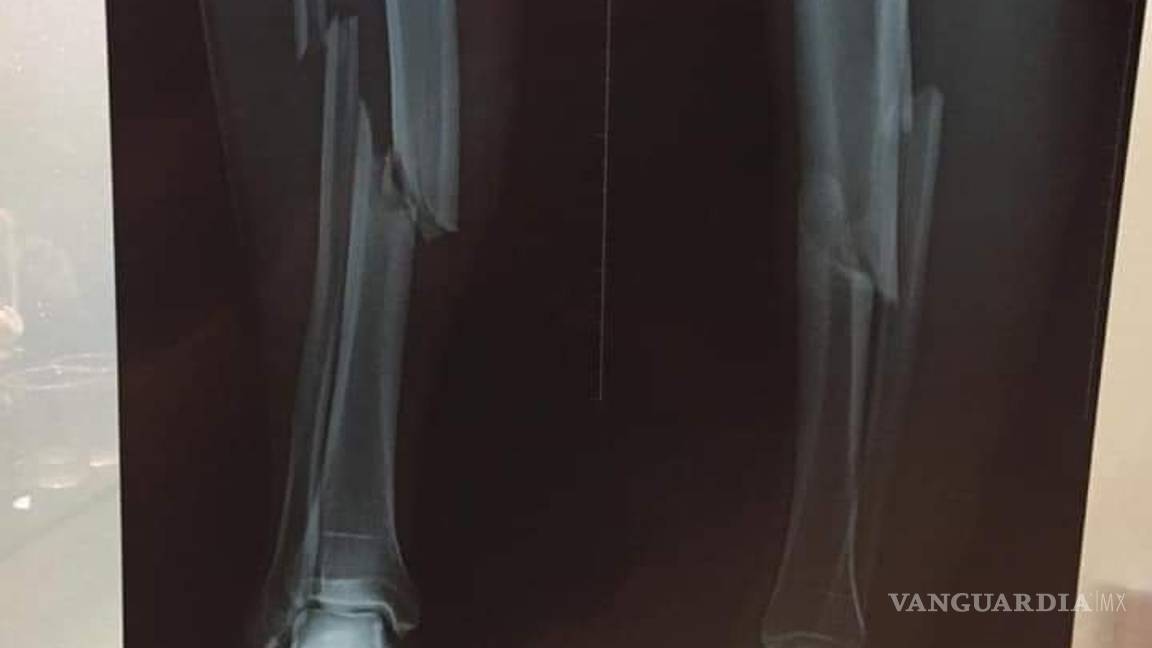

Mateo Zoch enfrenta fractura de tibia y peroné tras haber sido barrido por su rival, Leonardo Urapuca

Una escalofriante lesión se presenció en Bolivia cuando Leonardo Urapuca, del Blooming, le dio una fuerte entrada a Mateo Zoch, del Royal Pari, lo que resultó en doble fractura para el agraviado.

Corría el minuto 78, el marcador iba 2-2, y en un balón dividido, Urapuca le llegó a Zoch con los tacos de frente, provocando ruptura de tibia y peroné al mediocampista boliviano.